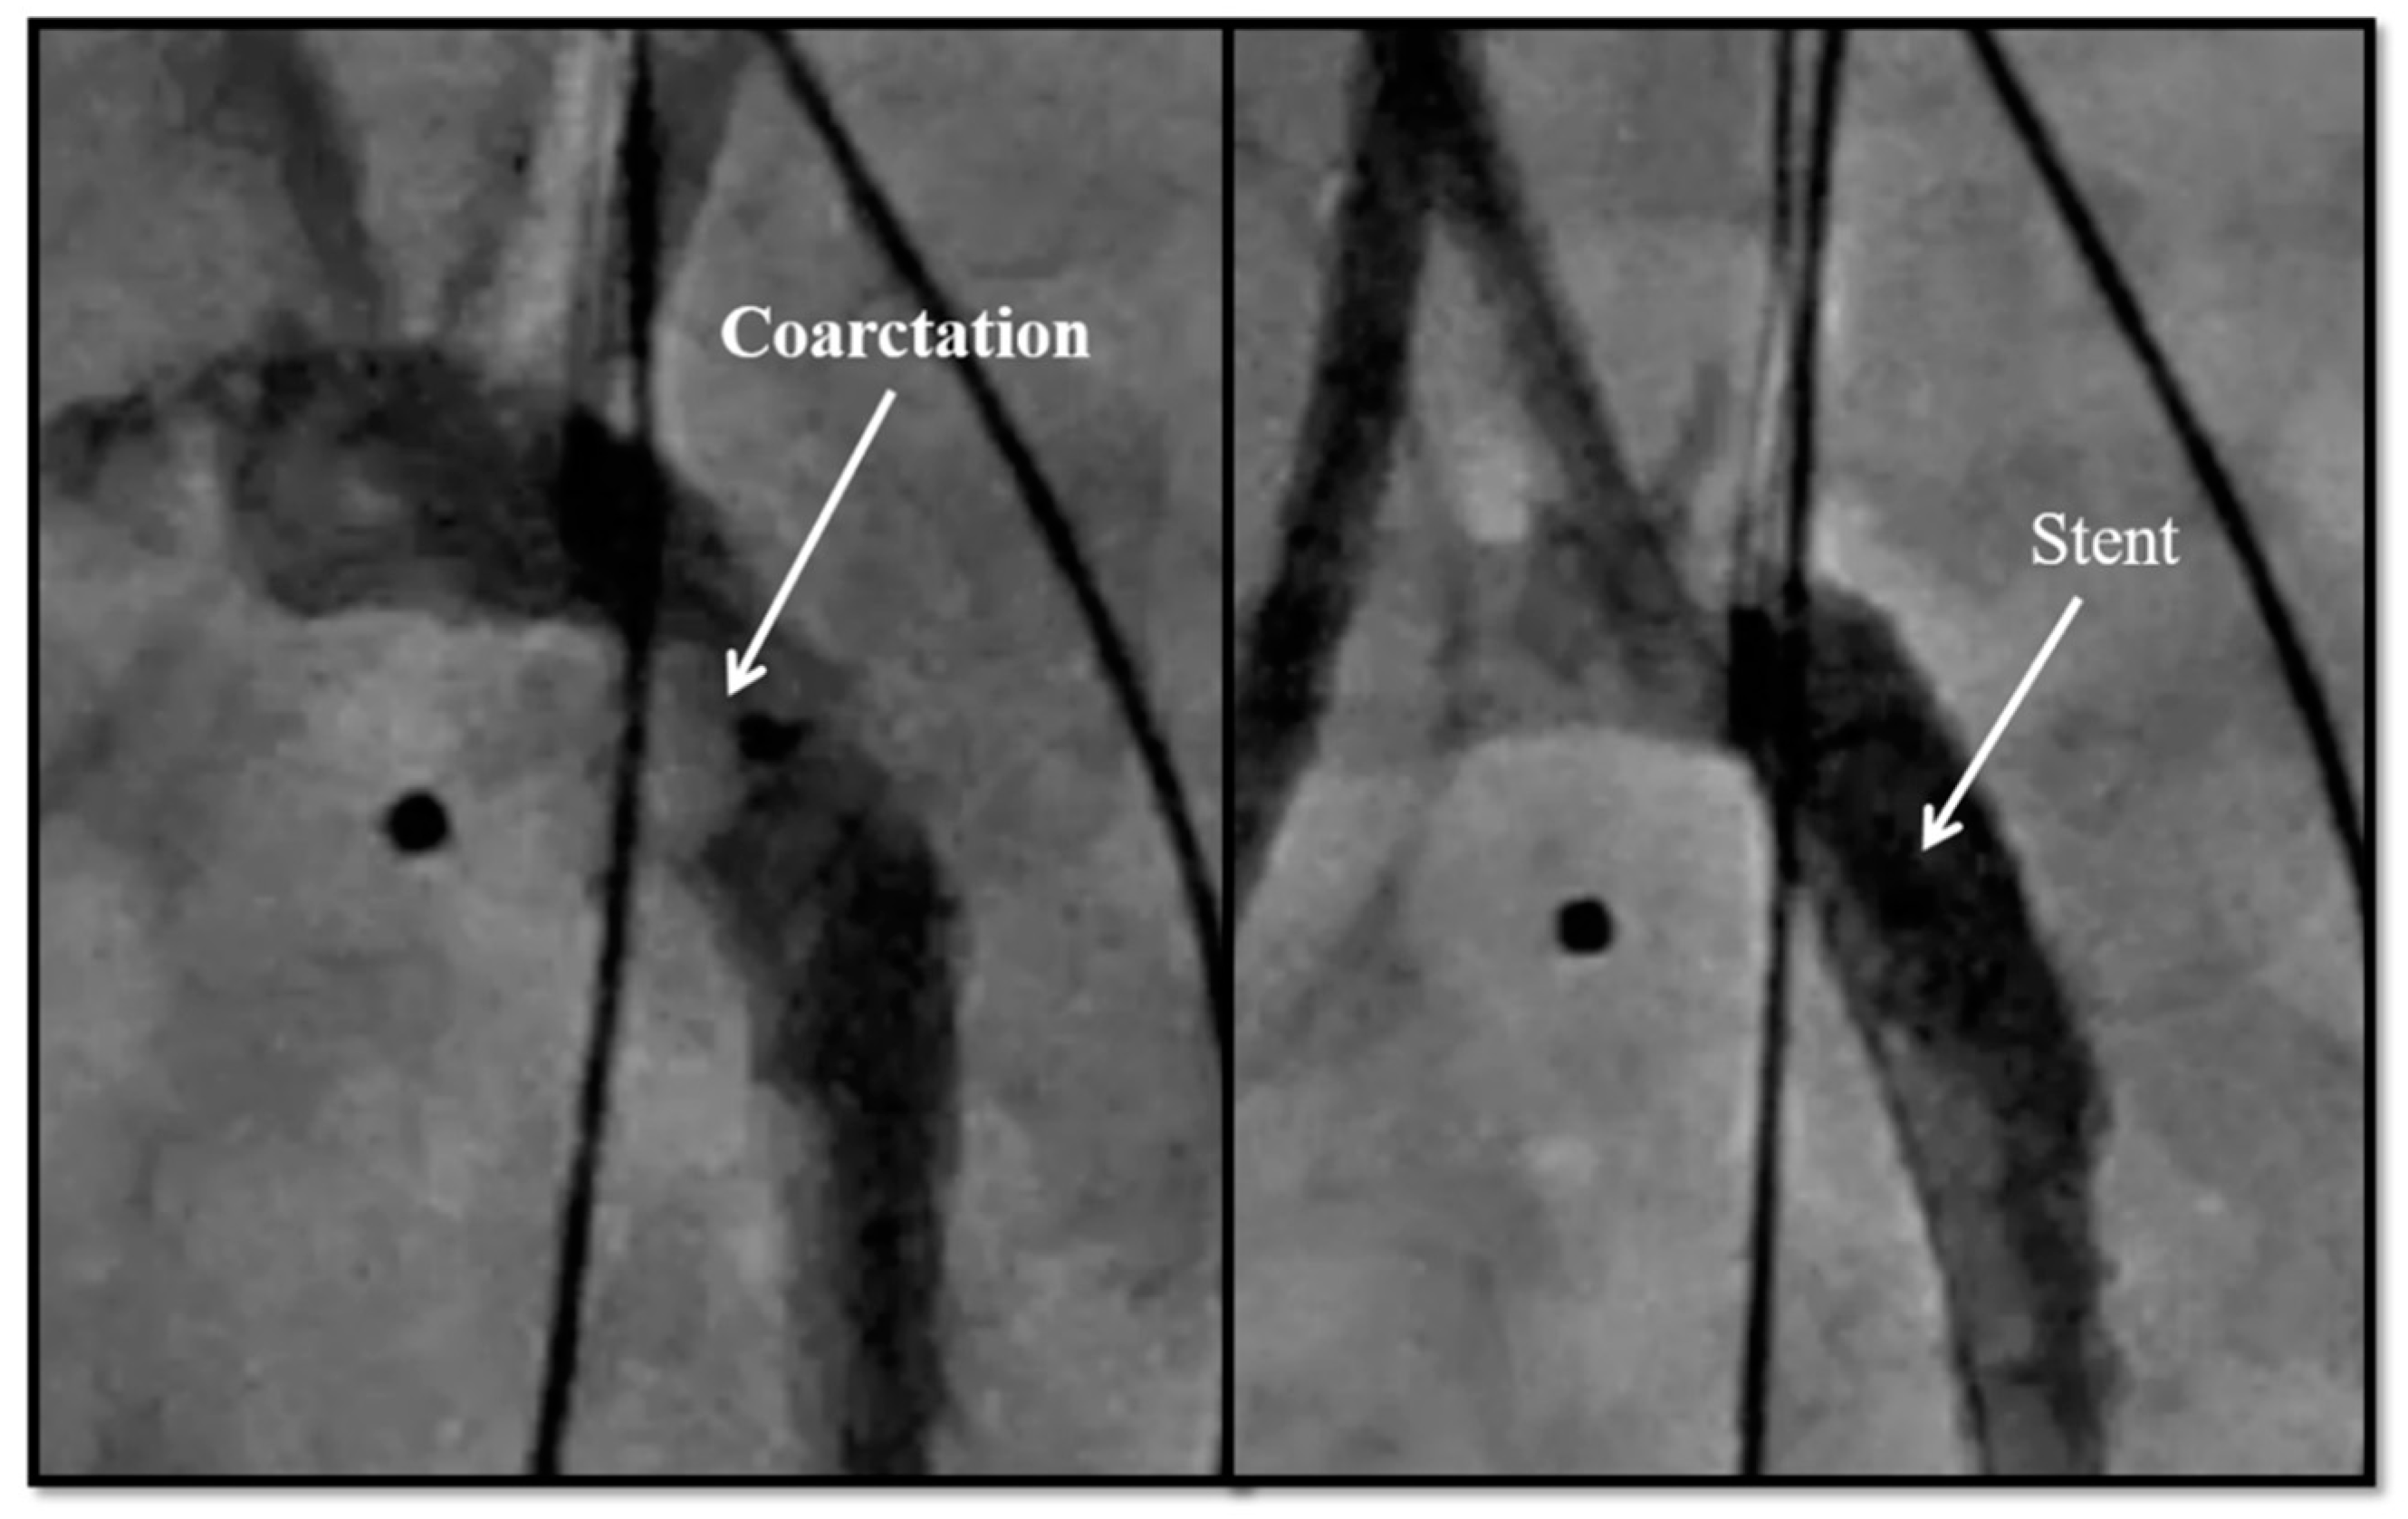

| 5. Coarctation of the aorta stent | 6 |

| 5. Coarctation of the aorta stent | 6 | 0 | 1 | 3 |